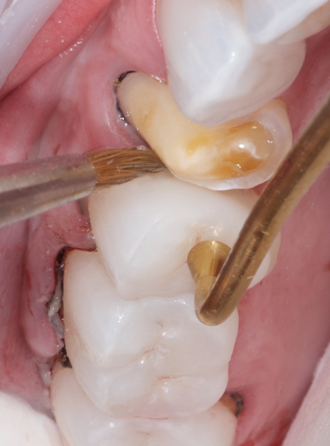

(5.) Step C: the restorations are inserted with a dual-cure composite resin, and the excess composite material is cleaned with a sable brush.

Figure 5